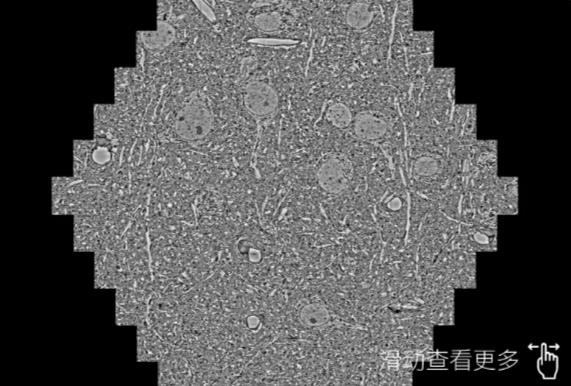

鼠脑切片。左图使用宝鸡蔡司宝鸡扫描电镜MultiSEM706对165μmx143pm面积区域成像,耗时仅需1.5秒。右图为鼠脑切片中30μm区域放大效果。样品由芝加哥大学B.Kasthuri提供。

使用蔡司高速宝鸡扫描电镜MultiSEM对1mm²人脑皮层组织进行高分辨成像,并对其中的各种细胞结构进行三维重构分析。左图展示了2x3mm²组织平面中锥体神经元的三维重构效果。右图显示了局部体积神经元三维重构。图像由哈佛大学chtman实验室提供,渲染图由D. Berger 制作。